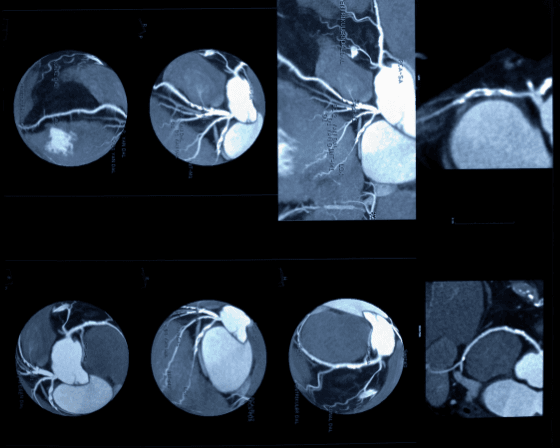

In the simplest terms, Angiography is an imaging test. It evaluates the blocks, narrowing, malformation, or enlarging of vessels, i.e., the arteries or veins present in our heart. This is done using a contrast liquid dye and a thin, flexible tube termed as a catheter.

We learn the extent and severity of heart disease by this procedure. An angiogram is an image taken with the catheter and can be done with the access point from the groin or arm.

An angioplasty is a minimally invasive procedure meant to remove plaque buildup in the walls of the arteries. Plaque buildup happens when cholesterol is collected in the blood. It widens the obstructed blood vessel and enables smoother blood flow. Angioplasty is also called percutaneous coronary intervention (PCI). There are different types of angioplasty, such as Angioplasty balloon procedure, Atherectomy of the artery, Stent placement surgery, Rotablation procedure, and Cutting Balloon Angioplasty.

Balloon angioplasty is a popular procedure for removing blocks in the heart. It involves using a catheter with a balloon tip to be inserted through an artery and enlarging a narrowing artery. After inflation, it is passed through the block to widen the artery and normalize blood flow. Then the tip is deflated and slowly removed. Angiography is constantly done to examine the area for normal heart function.